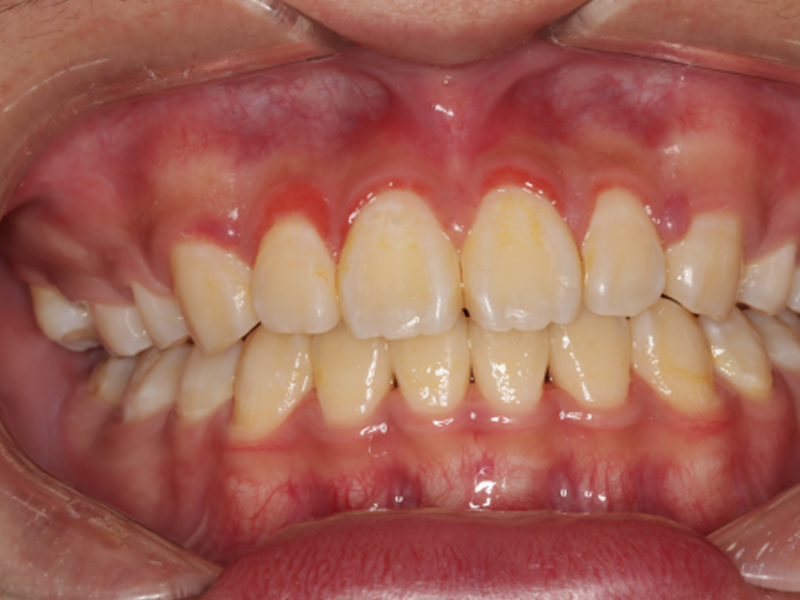

临床检查全口口腔卫生状况较差,视诊观察牙齿表面有牙菌斑和牙结石以及牙龈的颜色、状态。OHI-S=3,GI=2,牙龈轻度红肿,呈鲜红色,龈上结石(+),龈下牙石未探及,PD=2-5mm,GR=0mm,AL=0mm,TM=0。诊断为菌斑性龈炎。

患者术后无牙龈不适,无明显疼痛感,1-2天后出血、破溃愈合,牙龈红肿逐渐消失。全口牙行超声龈上洁治术后一周牙龈红肿消退,牙龈色粉红,质地坚韧,探诊出血阴性。通过询问患者日常刷牙及维护牙齿的方法,发现患者已逐步养成良好的口腔卫生习惯,早晚正确刷牙,合理使用牙线和牙签。定期复诊,指导患者半年到一年需要常规洗一次牙。